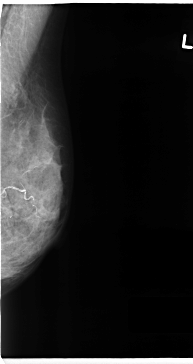

C_0125_1.RIGHT_CC

RIGHT_CC LINES 4712 PIXELS_PER_LINE 2720 BITS_PER_PIXEL 12 RESOLUTION 50 OVERLAY

FILE: C_0125_1.RIGHT_CC.OVERLAY

TOTAL_ABNORMALITIES 1

ABNORMALITY 1

LESION_TYPE MASS SHAPE OVAL MARGINS ILL_DEFINED

ASSESSMENT 4

SUBTLETY 2

PATHOLOGY MALIGNANT

TOTAL_OUTLINES 1

BOUNDARY